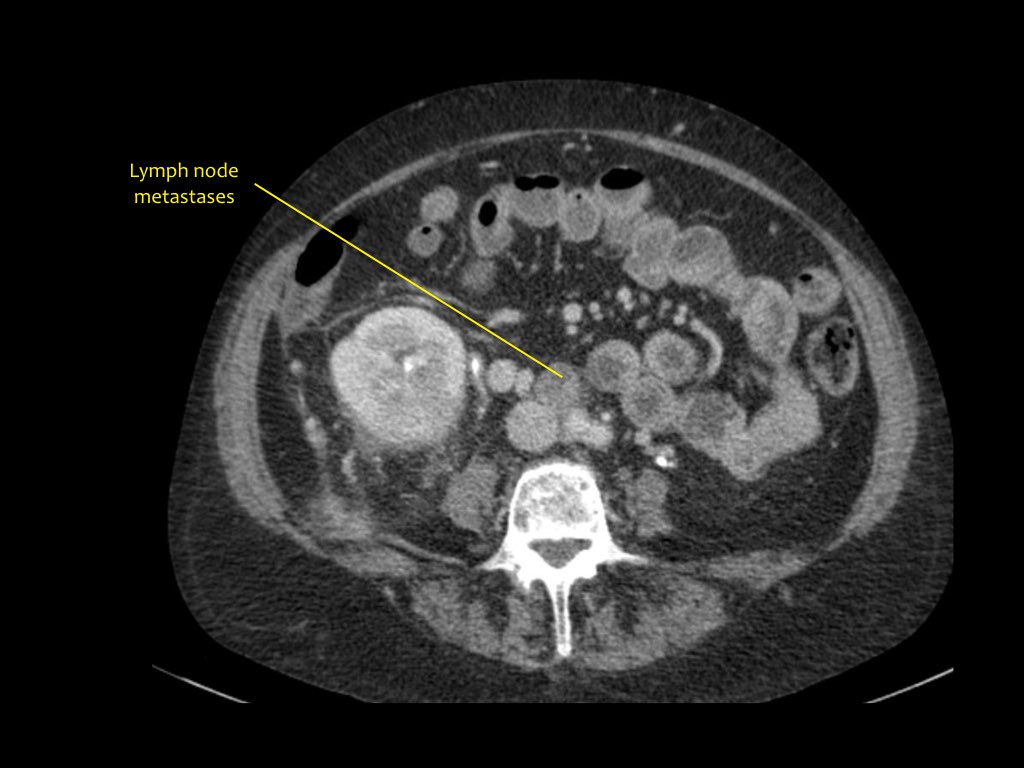

Tổn thương xâm lấn ở cực dưới thận phải, phát triển đáng kể sau sáu tháng, kèm theo hạch bạch huyết lan rộng. Đây được xác định là di căn của ung thư phổi.

Có một tổn thương di căn ở thận trái và nhiều tổn thương di căn hạch bạch huyết (mũi tên).

Nếu đây là biểu hiện duy nhất, sẽ rất khó để phân biệt với ung thư biểu mô tế bào thận có di căn hạch bạch huyết.